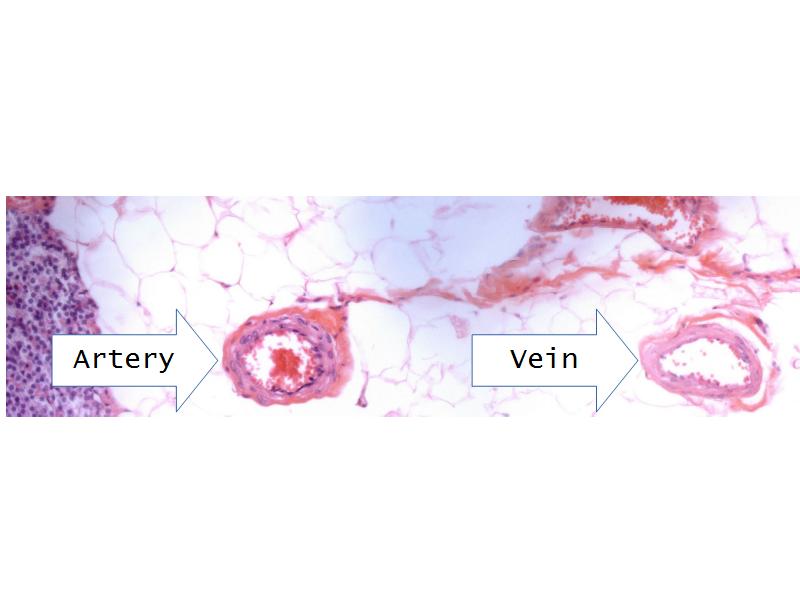

- Parathyroid glands

- Slide 54: Parathyroid glands